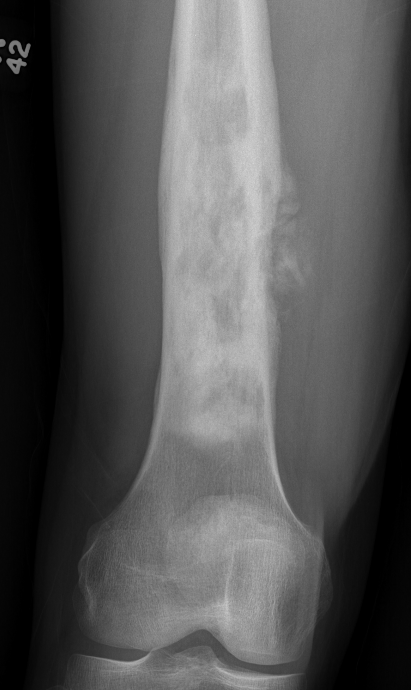

Osteosarcoma of the distal femur

Osteosarcomas of the proximal tibia

Xray

Typically metaphysis of long bones

- distal femur 35%

- proximal tibia 20%

- proximal humerus 10%

Can be diaphysis / axial skeleton

Features

- new bone formation / osteoid

- permeative cortical destruction

- wide zone of transition

- periosteal reaction

- soft tissue mass